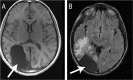

Figure 1A&B:

A: Magnetic resonance imaging of the brain of a 12-year-old immunocompetent child showing a large right occipital mass (arrow) with heterogeneous enhancement, perifocal oedema in the right temporal and parietal lobes and a midline shift to the left. The nasal sinuses were clear. B: Post-resection computed tomography showing debulking of the right-sided occipital fungal mass (arrow) two days later. Note the regression of the perilesional reactive changes with a persistent mild midline shift to the left and regression of the right trigone effacement.